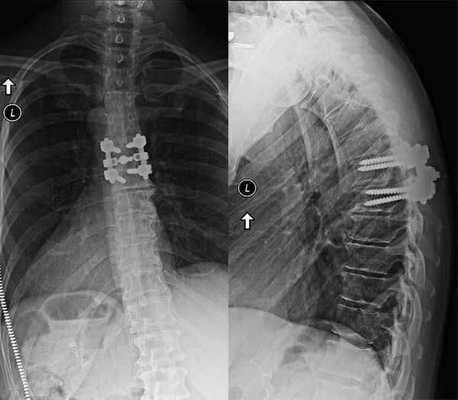

MIS—минимально инвазивное вмешательство; TLIF—трансфораминальный межтеловой спондилодез. Интраоперационная флюорограмма в прямой проекции после установки межтелового импланта:

в данном случае имплант установлен с использованием бокового доступа с выпуклой стороны деформации.

L—левый бок пациента. У данной 65-летней пациентки на фоне ранее перенесенных ляминэктомии L4-L5 и заднебокового спондилодеза развилось дегенеративное поражение смежных позвоночно-двигательных сегментов.

А. На сагиттальном МР-скане в режиме Т2 — признаки спондилолистеза 1 степени и дегенеративного поражения межпозвонкового диска.

Б. На аксиальном МР-скане в режиме Т2 признаки выраженной дегенерации и гипертрофии дугоотростчатых суставов.

В. Рентгенограмма в положении стоя в боковой проекции — спондилолистез L3-L4 первой степени и дегенеративные изменения замыкательных пластинок. Послеоперационные рентгенограммы в прямой (слева)

и боковой (справа) проекциях после прямого бокового межтелового спондилодеза L3-L4 и минимально инвазивной транспедикулярной стабилизации позвоночника. Аксиальный МР-скан в режиме Т2:

в данном случае значительные размеры поясничной мышцы делают боковой доступ к позвоночнику на этом уровне небезопасным.